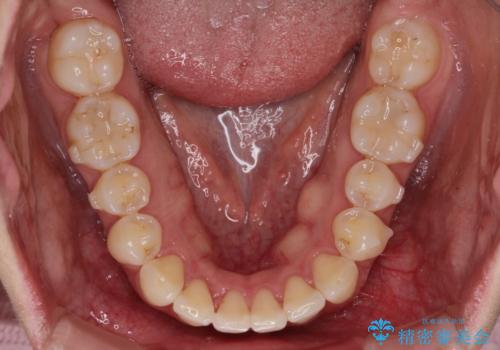

初診時の歯並びの状態としては、下顎前歯に及ぶの中等度のがたつき(叢生)があり、前歯が深く噛みこんでいる状態でした。

抜歯は行わず歯列弓の拡大やディスキング(歯と歯の間の隙間を作る処置)を行い叢生を改善しました。

見た目、嚙み合わせ及び、治療期間や施術内容に大変ご満足いただきました。